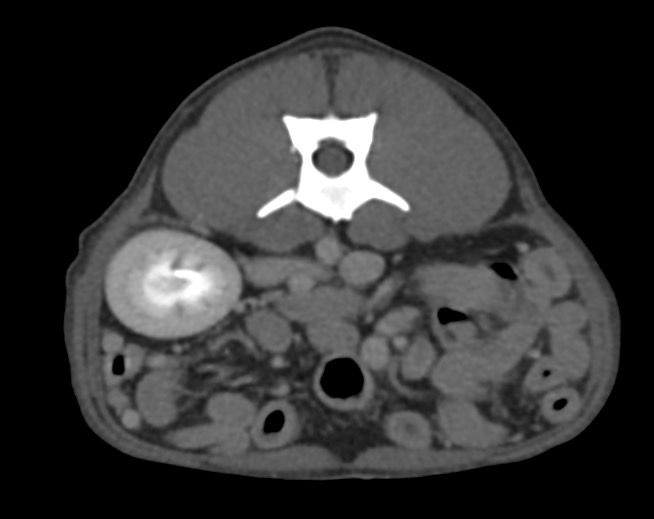

狗狗後腳癱瘓也有可能是血栓 不一定是骨骼神經肌肉問題喔

後肢癱瘓的柴柴經由他院轉診來築心做電腦斷層掃瞄因為狗狗以前病史有椎間盤突出問題

所以以為是脊椎問題想要來評估手術

掃瞄結果診斷為動脈血栓造成

主動脈血栓栓塞是一種急性且危及生命的疾病,當血液凝塊從心臟或其他部位脫落,經過血液循環流向並卡住動脈中的某些血管,造成局部的血液供應中斷、相應部位的器官或組織缺氧,將引起疼痛、損傷甚至壞死。

臨床上可藉由理學檢查、血液學檢查、超音波、電腦斷層等方式來確診犬主動脈血栓栓塞

此患犬在電腦斷層影像以及後續追蹤的超音波下都可見明顯血栓影像